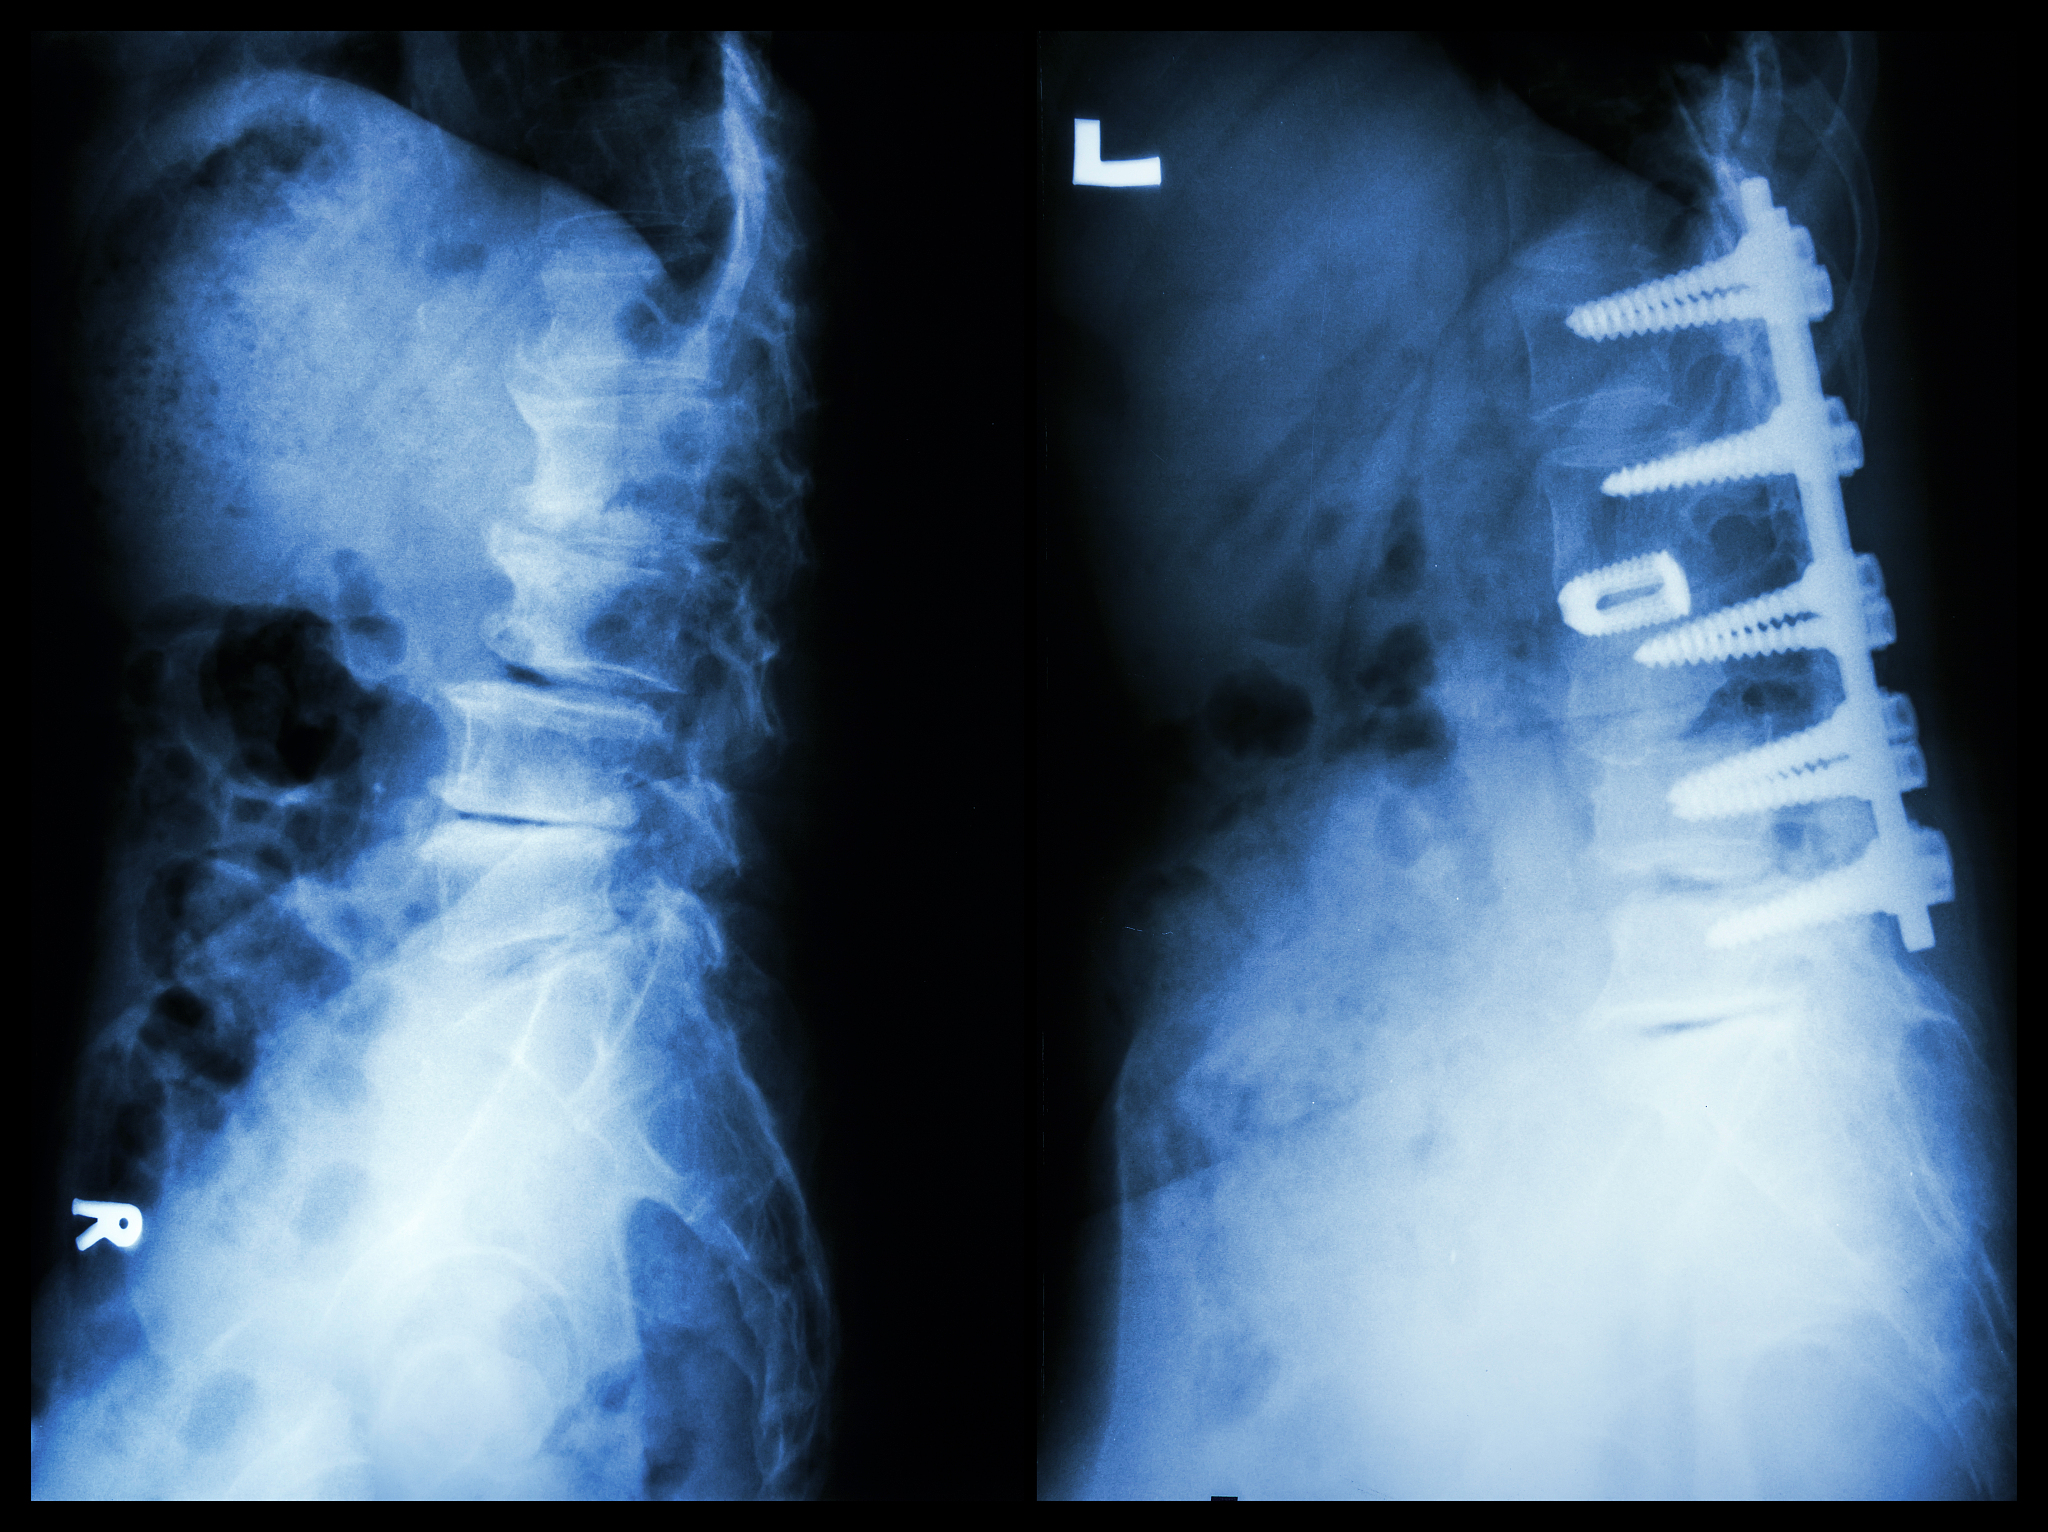

椎体成形术(vertebroplasty)是一种常见的治疗椎体骨折的微创手术。它通过在椎体骨折部位注入骨水泥,来稳定椎体并缓解疼痛。

1. 椎体骨折:主要适用于由于骨质疏松、肿瘤、骨转移等原因引起的椎体骨折,可有效减轻疼痛并恢复患者的活动能力。

2. 椎体压缩性骨折:适用于椎体因骨质疏松、骨质增生等原因导致的椎体压缩性骨折,可以恢复椎体高度并改善症状。